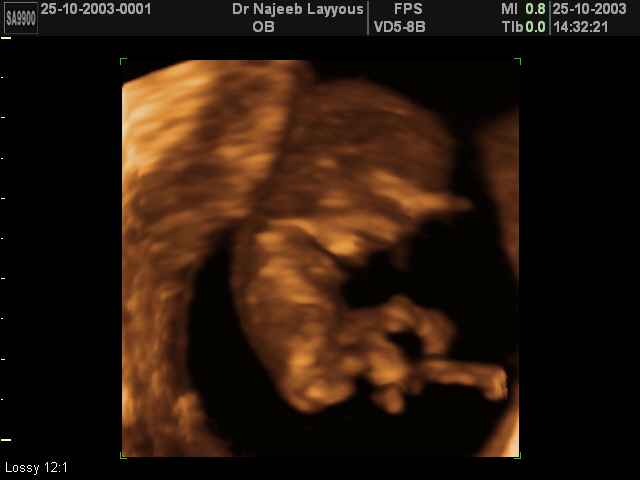

- First Trimester Ultrasound Photos

3D First Trimester Ultrasound Scan Photos ( Early Pregnancy Ultrasound Photos ) | Dr N Layyous